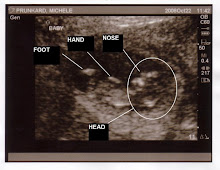

We did have another doctor visit last week. We got to hear the heartbeat, all 140 beats per minute of it. It's a wonder you can hear anything out of the $5 Osco Karaoke machine they use to amplify the heartbeat. It's all scratchy like a shaving cream commercial or something. It was neat to hear and made us feel good that things are rolling along. We have another appointment on December 9, with another sonogram that day as well. HOPEFULLY, we'll get a shot at seeing what sex the baby is. Keep your fingers crossed.